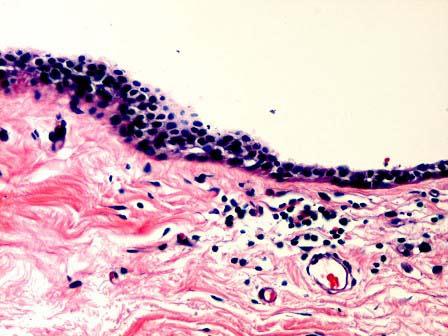

问题 女性,35岁,左乳头红肿触痛半月余,溢液一周。乳晕下扪及边界不清硬结,切除左乳送检,大体见乳头乳晕下区数条输乳管扩张扭曲,管腔扩张,直径12cm,管腔内充满棕黄色糊状物,管周有灰白色纤维性厚壁。镜下见乳腺小叶间质内出现扩张的导管,管腔内见脱落上皮细胞及脂质分泌物,导管周围纤维组织增生伴淋巴细胞浸润(如图)。应诊断为 ( )

选项 A.乳腺导管扩张症 B.乳腺导管增生 C.乳腺导管原位癌 D.乳腺小叶增生 E.以上都不是

答案 A